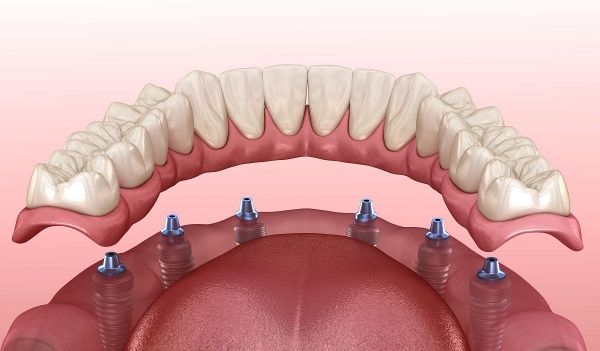

刘本义院长擅长各类种植牙项目,无论是常规单颗、多颗种植,还是高难度的all-on-4、穿颧穿翼种植,都能稳准完成,技术覆盖全场景缺牙修复需求。

3、临床中,他曾为83岁高龄患者(其父亲)成功完成种植手术,以极致细致的操作兼顾可靠性与疗效;还为全口无牙的71岁刘爷爷实施即刻负重种植,让老人当天就能变好咀嚼功能,重新品尝美食。